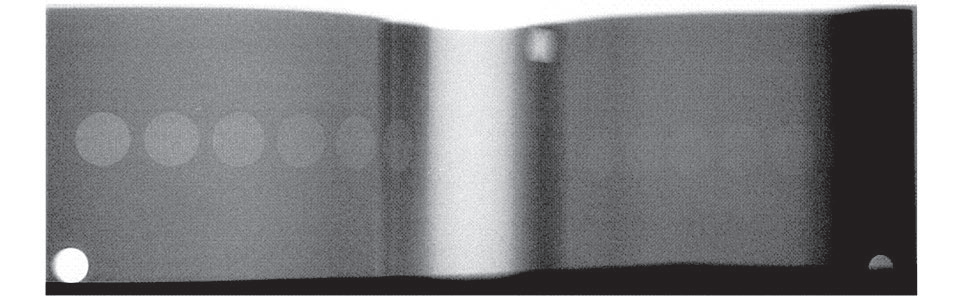

將低對(duì)比度分辨力模體放置在三腳架上固定, 并處在照射野的中心位置,選擇合適的曝光條件或自動(dòng)曝光條件成像,如下圖 。對(duì)于膠片成像的,在膠片上直 接觀察能分辨的最低對(duì)比度值 ;對(duì)于數(shù)字成像的,需調(diào) 整窗寬窗位使顯示影像達(dá)到最佳,再觀察能分辨的最低 對(duì)比度值。

圖1 低對(duì)比度分辨力影像